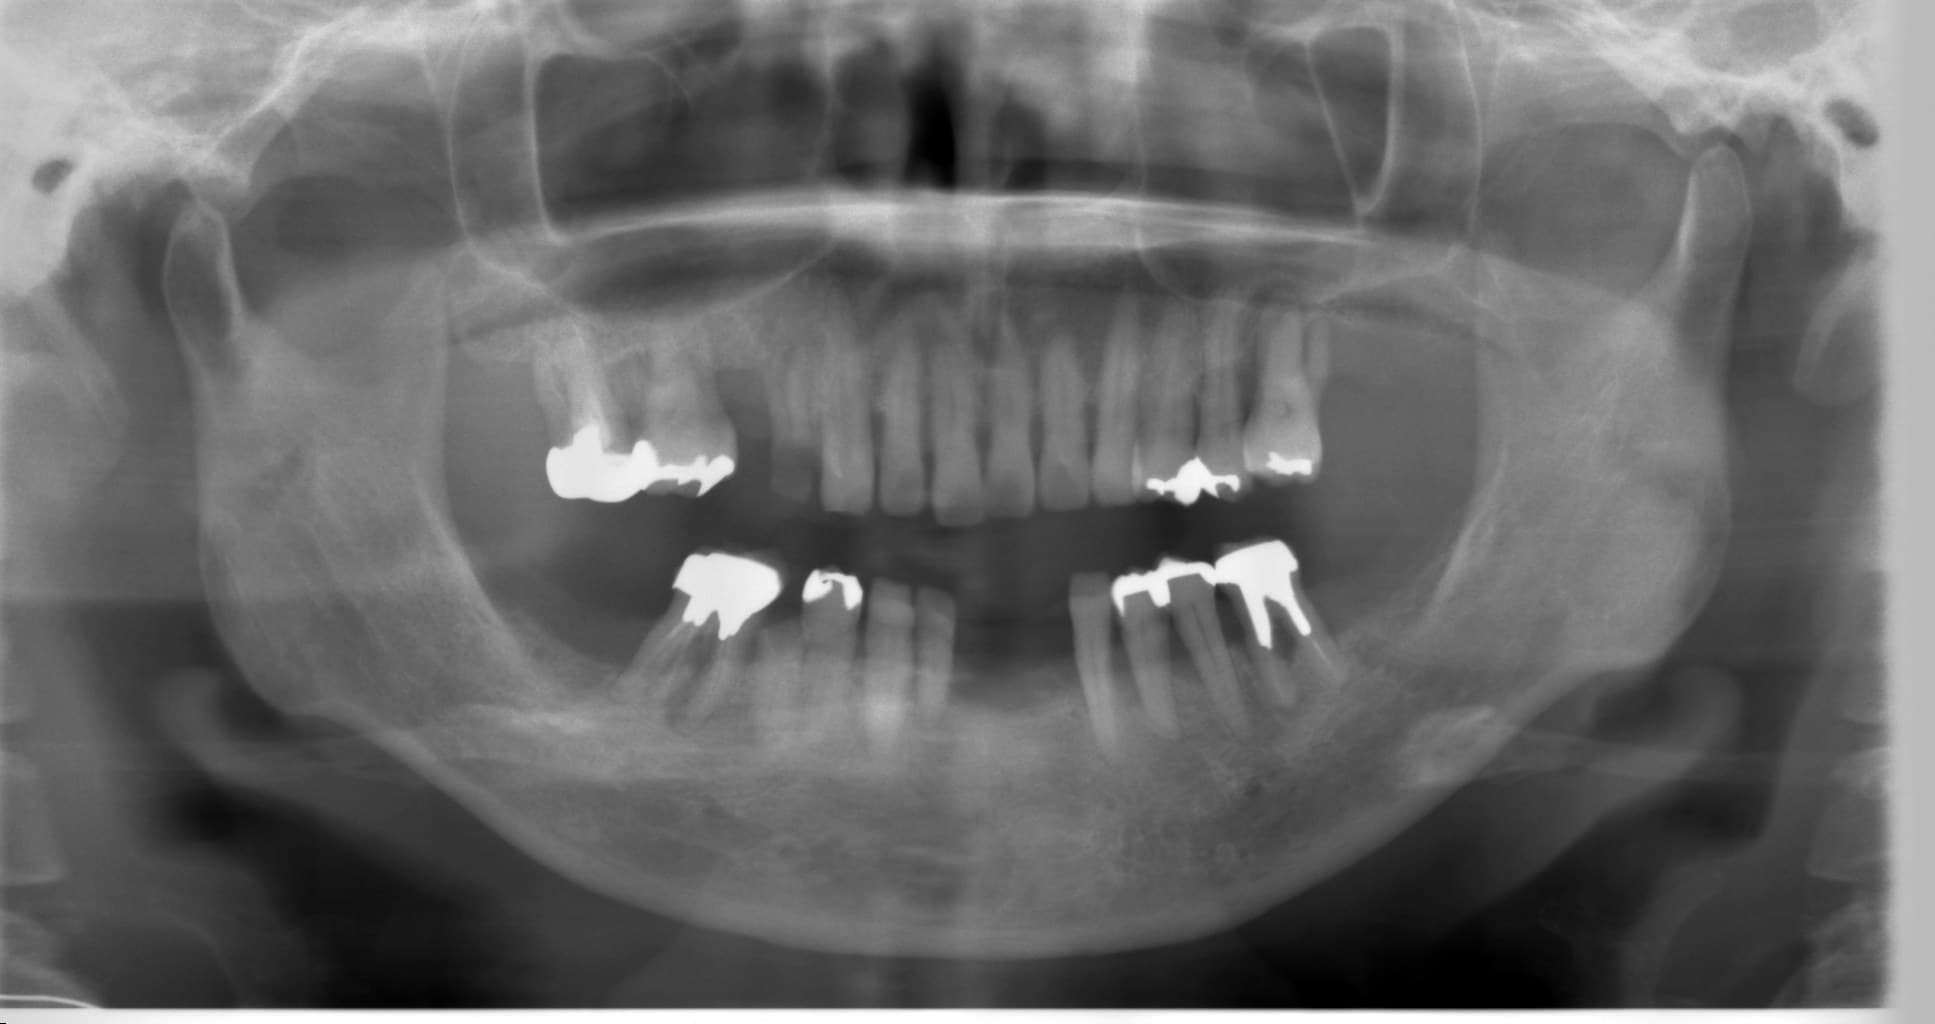

歯周病治療を行った症例をご紹介します。

50代の女性の方です。

以前から歯がぐらついてきて、そのたびに歯医者に通い歯を抜いていたそうです。

治療に行く度に抜歯をする中で、「どうしても、自分の歯で生活をしたい」という思いが芽生え、来院してくださいました。

重度の歯周病で、出血があり歯もグラグラして、歯周ポケットは5~8mmと深くありました。

初診時から3年経った現在も、グラグラや出血は落ち着き、大変おきれいにセルフケアを続けて頂いています。